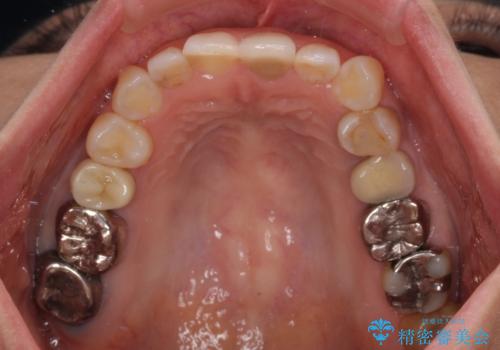

- 上下前歯のデコボコを気にして来院された患者様です。

カウンセリングにて詳しく話を聞いたところ、一番気になっているのは下顎前歯の叢生であり、上顎犬歯はあまり気になっていないとのことでした。

装置としては、叢生の程度が強くなかったため、インビザラインの廉価版であるモデレート・パッケージを使用することとしました。

上顎は、失活して歯の色が変色しているため、将来的に補綴治療で自然な口元に仕上げていきたいとのことでした。